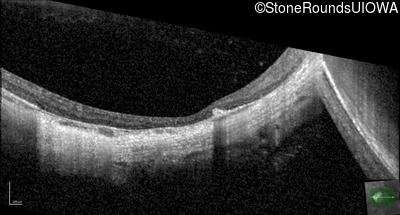

Optical Coherence Tomography - Left - 20/40

Exemplar / OCT Stack

OCT Stack